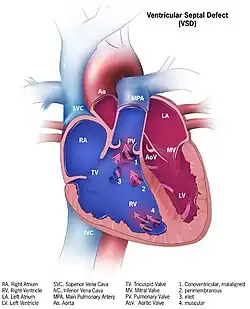

| |

| Illustration showing various forms of ventricular septal defects. 1. Conoventricular, malaligned 2. Perimembranous 3. Inlet 4. Muscular | |

Although there are several classifications for VSD, the most accepted and unified classification is that of Congenital Heart Surgery Nomenclature and Database Project.[14] The classification is based on the location of the VSD on the right ventricular surface of the inter ventricular septum and is as follows:

Multiple

Type 1

Type 1 is sub aortic

Type 2

- Type 2 also known as perimembranous, paramembranous, conoventricular, membranous septal defect, and subaortic.

- Most common variety found in 70%

Type 3

Type 3 also known as inlet (or AV canal type).

- Commonly associated with atrioventricular septal defect, found in about 5%

Type 4

Type 4 also known as muscular (trabecular)

- Located in the muscular septum, found in 20%. Can be sub classified again based on the location into anterior, apical, posterior and mid

Type: Gerbode

Type: Gerbode also known as left ventricular to right atrial communication

- Due to absence of Atrioventricular septum.

Heart anatomic view of right ventricle and right atrium with example ventricular septal defects

Heart anatomic view of right ventricle and right atrium with example ventricular septal defects -